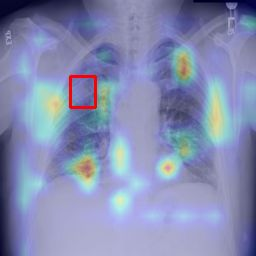

Deployments of artificial intelligence in medical diagnostics mandate not just accuracy and efficacy but also trust, emphasizing the need for explainability in machine decisions. The recent trend in automated medical image diagnostics leans towards the deployment of Transformer-based architectures, credited to their impressive capabilities. Since the self-attention feature of transformers contributes towards identifying crucial regions during the classification process, they enhance the trustability of the methods. However, the complex intricacies of these attention mechanisms may fall short of effectively pinpointing the regions of interest directly influencing AI decisions. Our research endeavors to innovate a unique attention block that underscores the correlation between 'regions' rather than 'pixels'. To address this challenge, we introduce an innovative system grounded in prototype learning, featuring an advanced self-attention mechanism that goes beyond conventional ad-hoc visual explanation techniques by offering comprehensible visual insights. A combined quantitative and qualitative methodological approach was used to demonstrate the effectiveness of the proposed method on the large-scale NIH chest X-ray dataset. Experimental results showed that our proposed method offers a promising direction for explainability, which can lead to the development of more trustable systems, which can facilitate easier and rapid adoption of such technology into routine clinics. The code is available at www.github.com/NUBagcilab/r2r_proto.